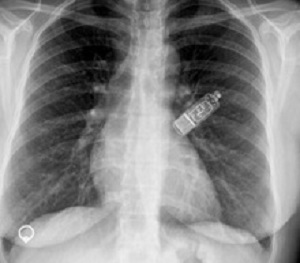

Minimally invasive prolonged electrocardiographic monitoring with small, insertable cardiac monitors (ICMs) placed under the skin could assist with early AF diagnosis and earlier treatment. Dr James A Reiffel, of the Columbia University College of Physicians and Surgeons, New York, and colleagues conducted a study in which 385 patients received an insertable cardiac monitor.

Exposures: Patients underwent monitoring with an insertable cardiac monitor for 18 to 30 months.